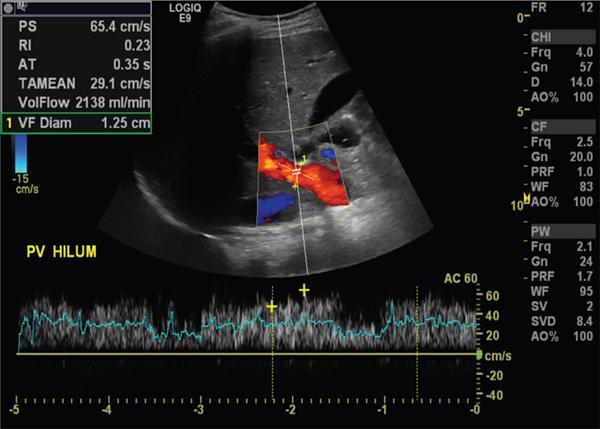

Imaging plays a significant role to make an early diagnosis and establish the best treatment options for posttransplant complications as clinical manifestations and laboratory parameters in many of the complications are usually nonspecific and overlapping. The imaging evaluation of postoperative complications remains the same in both types of liver transplants (DDLT and LDLT). Ultrasound with colour Doppler is usually the first modality of choice in the immediate postoperative period due to its easy and bed side availability with high accuracy and ability to pick up all major posttransplant complications, though it has a drawback of being operative dependent. It is usually part of regular postoperative assessment of the recipient for initial few postoperative days, playing an important role in picking up early complications. It is essential for the radiologist to know the details of the individual patient’s postoperative anatomy and surgical details, since anastomoses are the locations where complications occur most frequently. Goals of ultrasound evaluation in early postoperative period: Vascular evaluation with colour Doppler: CT/MRI imaging plays a supportive role for confirmation of the findings seen on ultrasound or colour Doppler or is done as an advanced imaging in case of mismatch between clinical or laboratory parameter and ultrasound or Doppler findings. MRI is particularly important for assessment of the biliary tree. First postoperative Doppler is done within 24 hours of the surgery and it serves as the baseline for comparison in the future. The haptic artery needs to be evaluated at the anastomotic site and also in the intrahepatic portions and the parameters to be evaluated are the systolic upstroke, PSV and resistive index (RI). Table 9.14.16 gives normal ranges of these parameters. Normal hepatic artery Doppler waveform demonstrates rapid systolic upstroke, with a systolic acceleration time (SAT) of less than 0.08 second and continuous diastolic flow, displayed above the baseline. A wide variability is observed in PSV of HA in the immediate postoperative period even in the absence of any hepatic arterial complication. Normal values may vary averagely from 40 to 120 cm/s. Vascular kinks or anastomotic site oedema in postoperative period can lead to falsely increased PSV in the HA. Correction of Doppler angle must be kept in mind while measuring the PSV of HA so that the angle aligns with the direction of the artery and must be less than 60 degrees to avoid inaccurate results. The hepatic arterial RI is an important tool to assess the hepatic arterial waveform in postliver transplant setting, as it allows semiquantitative estimation of the resistance to arterial flow into the liver. The normal RI ranges from 0.55 to 0.80 in posttransplant patients. The RI increases with decrease in the diastolic flow in the hepatic artery, which suggests increased resistance to the hepatic arterial flow. Absence or reversal of diastolic flow in the hepatic artery corresponds to an RI of 1.0 It is important to note that, increased RI of the hepatic artery (greater than 0.8) is a normal findings in the first few days after liver transplantation, due to decreased diastolic flow, which is attributed to allograft oedema, increased cold ischemia time, increased portal flow or vessel spasm. These transient arterial waveform abnormalities in early postoperative period usually resolve and normalize in 7–15 days on the follow-up Doppler studies. In view of significant variability in the PSV and RI of the hepatic artery in immediate postoperative period, other than in cases of absent arterial flow, the diagnosis of a hepatic arterial complication is seldom established on the basis of a single postoperative Doppler ultrasound. Arterial waveform abnormalities on the immediate postoperative scans should be followed closely and correlated with the patient’s clinical findings including liver function tests. Persistence of the abnormalities on serial follow-up Doppler studies or further deterioration of the waveform suggest presence of arterial complications. A decrease in hepatic arterial RI (RI < 0.55) is a more ominous finding than increased RI and is usually a concern for serious arterial complications like HA stenosis or impending thrombosis. The SAT – the interval from end-diastole to the first systolic peak – is a measure of the rapidity of the upstroke and normally should not exceed 0.08 seconds (Fig. 9.14.27). Portal vein evaluation needs to be done on greyscale ultrasound as well as on the colour Doppler. The presence of echogenic thrombus or filling defect is better appreciated on the greyscale ultrasound images. The PV peak velocity (measured at the anastomotic site) is the most important parameter for Doppler evaluation along with spectral waveform analysis. The normal portal vein flow after liver transplantation is hepatopetal, monophasic with respiratory plasticity (Fig. 9.14.28). The portal venous velocity is variable and tends to decrease on serial examinations after transplantation. During the early postoperative phase, turbulent flow with high velocities may be a normal finding which tend to decrease on serial examinations. Hepatic veins reveal a triphasic waveform (Fig. 9.14.29) due to transmission of cardiac pulsations. Though loss of triphasicity is seen in HV stenosis, it is a very nonspecific finding and biphasic or monophasic waveforms are often seen in normal posttransplant patients. Therefore, presence of hepatic venous triphasicity can exclude hepatic venous stenosis; however, loss of triphasicity does not imply presence of a hepatic venous complication. The terms early posttransplant complications is variably used in literature for period of first 1–3 months after the OLT. Table 9.14.17 summarizes post transplant complications in early and late post transplant period. Vascular complications are a common cause for allograft failure after hepatic transplantation. Early detection of the vascular complications is possible with the help of imaging, which can help reduce the incidence of graft failure. Table 9.14.18 below describes approximate timeline of various post transplant complications in post transplant period. Hepatic artery stenosis First three months Portal venous thrombosis Majority within four weeks Portal vein stenosis Usually late (>6 months) Hepatic venous stenosis Usually late (>6 months) Hepatic arterial complications are particularly significant in postliver transplant patients, as unlike native liver, the biliary tree of a transplant liver is entirely dependent on arterial blood from the hepatic artery. As a consequence, any hepatic arterial complication resulting in compromised hepatic arterial flow, particularly hepatic arterial thrombosis, has a devastating effect on the biliary epithelium, inducing ischemia resulting in biliary strictures, necrosis, abscesses and allograft failure. Hepatic artery complications include HAT, stenosis, and pseudoaneurysms. HAT is a common and the most catastrophic complication after orthotopic liver transplant, and it represents more than 50% of all arterial complications. According to the onset, HAT can be defined as early (within the first month) or late (later than one month). The incidence of early HAT is approximately 4%–12% in adults and 42% in children, and it is a major cause of graft loss (53.1%) and mortality (33.3%) in the early postoperative period. Thrombosis occurring after the first month or late HAT has a more insidious clinical course and is less devastating. Other than surgical technical causes like small calibre vessels or size discrepancy in the donor and recipient vessels, stenotic anastomosis, kinking; several nonsurgical causes have been described for HAT, which include ABO blood type incompatibility, increased cold ischemic time of the donor liver, acute rejection and sluggish flow through the hepatic artery. Initially, symptoms, signs and abnormal laboratory values are absent in early HAT, whereas reduced or absence of flow within the hepatic artery can be readily picked up by bedside Ultrasound and Colour Doppler evaluation (Table 9.14.19). Ultrasound is diagnostic in 92% of cases of HAT. Timely diagnosis of HAT allows for therapeutic interventions to restore the hepatic artery patency by vascular intervention or surgical reexploration to salvage the graft; if these measures fail retransplantation is needed in most cases. On Doppler ultrasound, acute HAT is diagnosed by: Graft oedema, systemic hypotension, and high-grade hepatic artery stenosis (HAS) can lead to false-positive sonographic diagnosis of HAT; whereas, false-negative sonographic findings may occur in presence of periportal arterial collateral formation in chronic thrombosis. CT or MRI with standard angiographic protocol are usually performed to confirm the diagnosis, which will reveal a complete cut off of the hepatic artery after the anastomosis (Fig. 9.14.30). Arterial anatomical variations like replaced recipient hepatic artery or any technical modifications used during arterial anastomosis need to be noted while reporting the angiography, which can guide the interventional radiologist in a better way. In late stages of HAT, hepatic arterial collaterals can develop. This collateral vessel flow can cause a dampened (tardus parvus) hepatic arterial waveform with a prolonged acceleration time (AT), similar to that seen in significant HAS. Presence of tardus parvus waveforms in the distal hepatic arteries is an ominous sign and must not be considered evidence of patency of the hepatic artery; it rather indicates the presence of either proximal stenosis or thrombosis. HAS has reported incidence of 5%–11% in posttransplant patients and is the second most common postliver transplant vascular complication. It usually occurs within 3 months of transplantation and most commonly involves the site of anastomosis. Risk factors for HAS are similar to those for HAT with few additional causes including clamp injury and intimal trauma from a perfusion catheter. If left untreated or undiagnosed, it can progress to HAT (Fig. 9.14.32) and related complications including hepatic ischemia, biliary complications, sepsis and ultimately graft loss. Treatment options aim at reestablishing adequate blood flow at the earliest either with angiographic intervention involving balloon angioplasty or stenting or with surgery if the previous measures are unsuccessful.